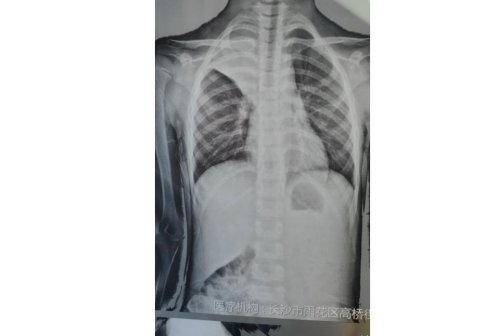

(南华大学附属长沙中心医院)驻点该社区的儿科专家、副主任医师余庆乐仔细询问了病史,并做了详细的体格检查,发现患儿右肺呼吸音明显偏低,完善胸片检查后发现星星整个右上肺不张,根据经验高度怀疑为肺炎支原体肺炎,并且很有可能出现了塑形支气管炎、痰栓堵塞等肺内并发症,需要尽快转上级医院住院治疗。

余庆乐一边安抚家长情绪,一边联系自己所在医院的儿科,让孩子从社区尽快转诊到医院。医院有专人接诊,快速安排了孩子住院,当天下午就进行了纤维支气管镜检查及治疗,镜下明显看到形似“树枝”状胶冻样分泌物,肺炎支原体抗体结果回报阳性,也证实了孩子感染了肺炎支原体肺炎,经过积极对症治疗后,星星终于康复出院,王女士悬着的心也终于落地了,出院后马上找到高桥街道卫生服务中心,对余庆乐医生当面表示感谢。